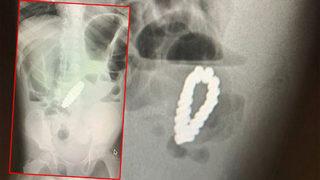

Karın ağrısı şikayetiyle hastaneye götürülen 4 yaşındaki çocuğun midesinden bilezik çıktı! Doktorlar bile ne olduğunu anlayamadı

Amerika Birleşik Devletleri’nde yaşayan 4 yaşındaki ismi açıklanmayan bir erkek çocuğu şiddetli karın ağrısı şikayetiyle aile tarafından hastanaye götürüldü. Dayanılmaz bir ağrı hisseden küçük çocuğun apandisitinin patladığını düşünen doktorlar cerrahi müdahale ile apandisitini aldı.